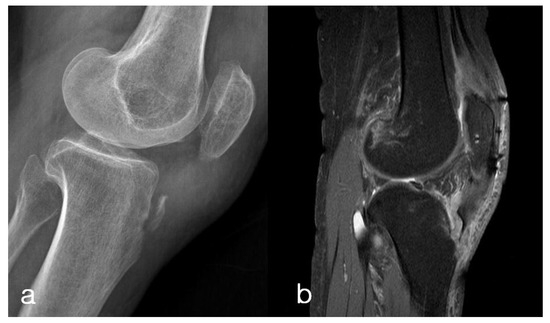

2. Case Presentation